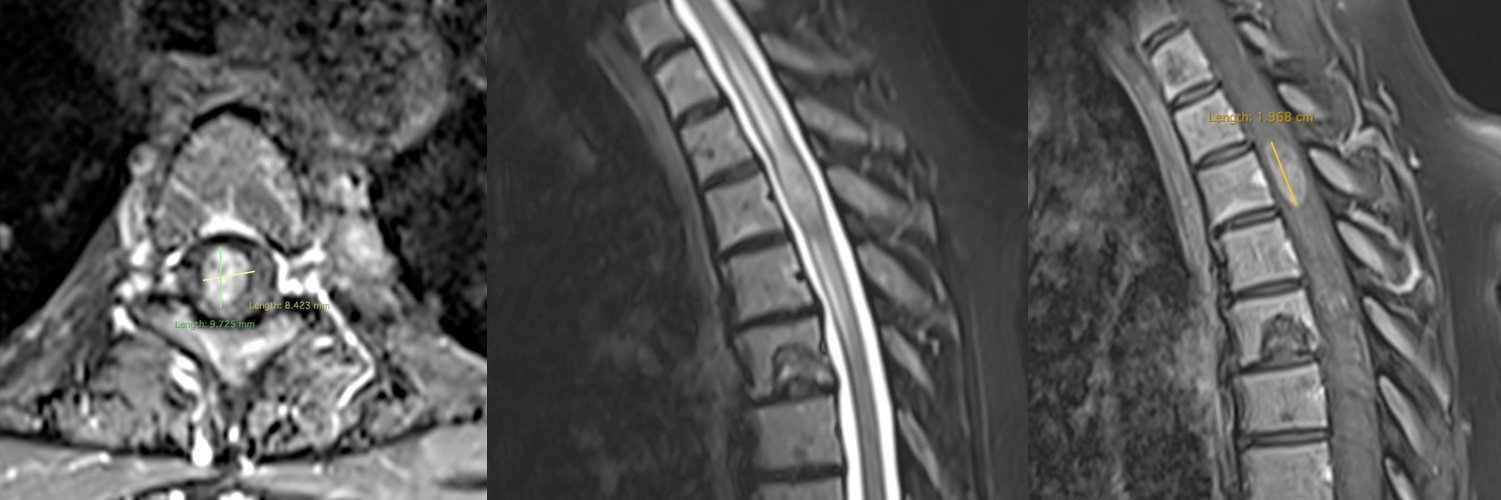

Meningiom spinal toracal – secțiuni sagitale

Meningiom spinal toracal – secțiuni axiale

Meningiom spinal toracal cu compresiune medulară severă